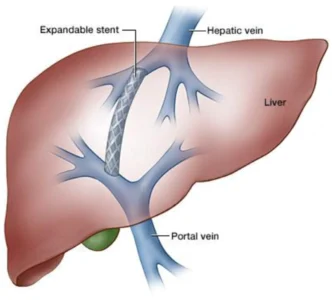

TIPSS (Transjugular Intrahepatic Portosystemic Shunt)

What is TIPSS?

TIPSS is a minimally invasive procedure used to treat portal hypertension, a condition where blood pressure in the portal vein becomes dangerously high due to liver disease.

During the procedure, a small channel is created within the liver using a stent. This channel allows blood to flow more easily through the liver, reducing pressure in the portal vein.

Conditions Treated

Severe portal hypertension

Recurrent variceal bleeding

Ascites (fluid accumulation in the abdomen)

Complications of liver cirrhosis

Benefits

Minimally invasive treatment

Reduces portal vein pressure

Controls internal bleeding

Improves liver circulation